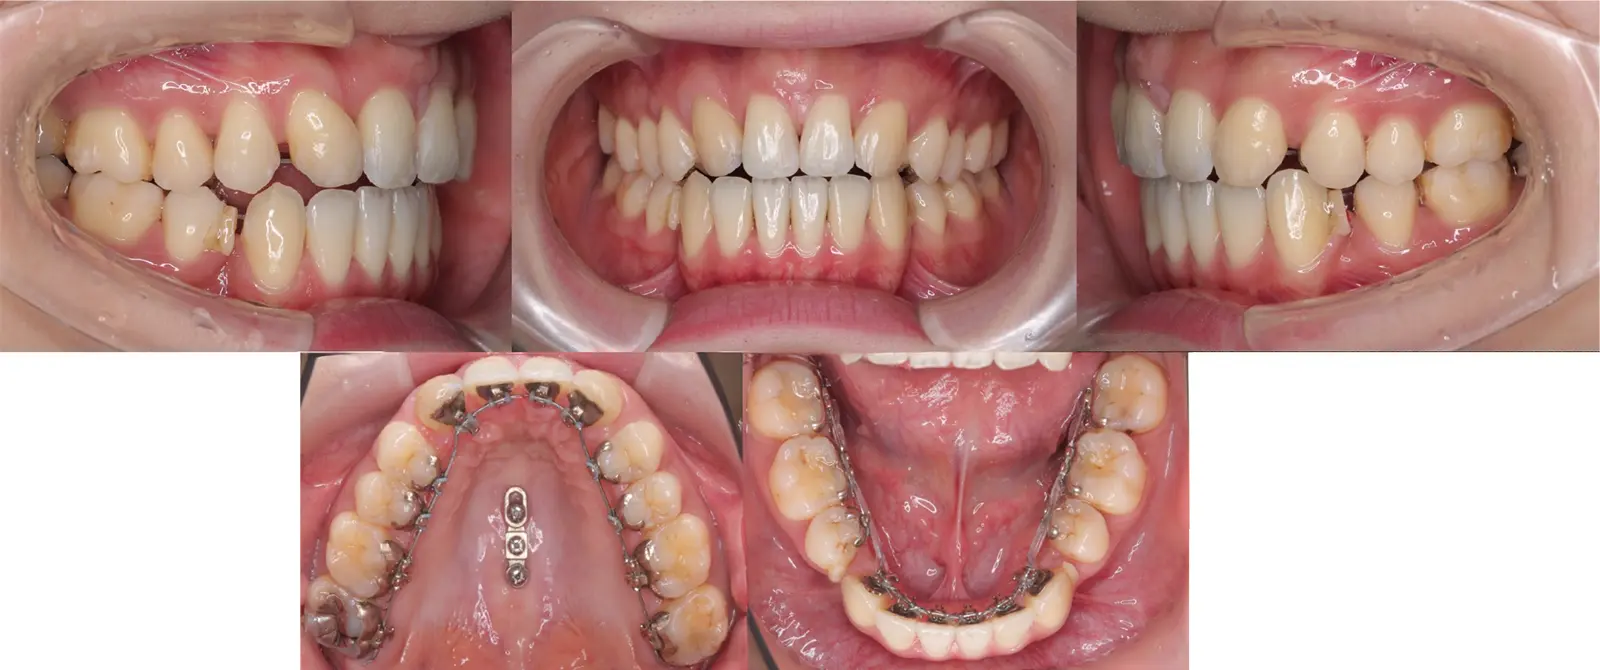

アングルⅡ級 叢生を伴う上顎前突症

- 主訴

前歯がかみ合わない、突出している

- 年齢

10代

- 治療期間

1年4ヶ月

- 治療回数

14回

- 治療に用いた主な装置

カスタムメイド型マルチブラケットタイプのデジタル矯正装置(インシグニア)

TAD(ミニスクリュー)を上顎臼歯部に植立

- 治療費

600,000円(税別)、調整料5,000円(税別)

※伊那分院にて治療

- 抜歯部位

上下顎第一小臼歯 計4本